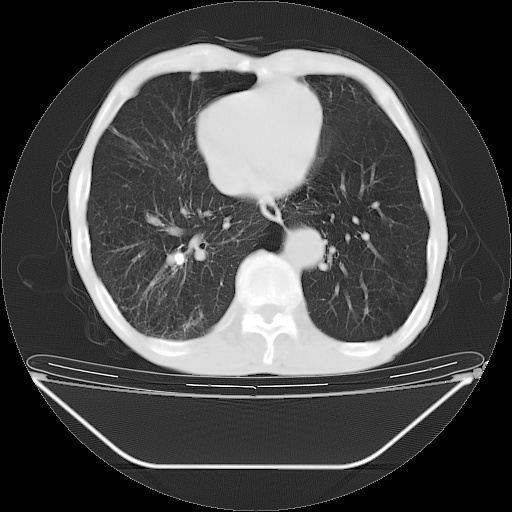

以下是引用zsl6918在2008-8-25 21:55:00的发言:[br]符合右肺周围性肺癌并肺内转移,左肺结核球。双肺肺气肿。腰椎附件转移。

以下是引用qc80012345在2008-8-26 6:14:00的发言:[br]符合右肺周围性肺癌并肺内转移,左肺结核球。双肺肺气肿。腰椎附件转移。